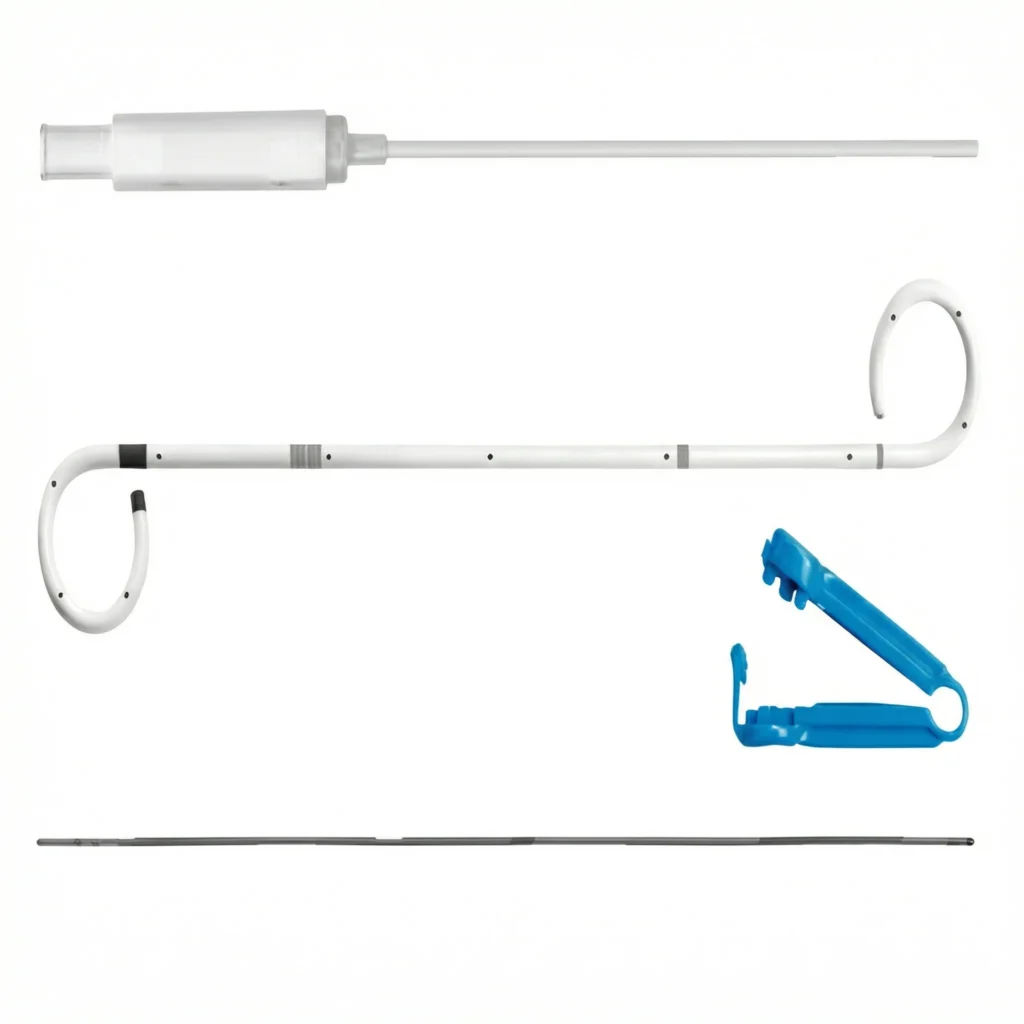

ARIA Wire Rapid Guid – Fio Guia Hidrofílico

Fio Guia Hidrofílico

O fio guia hidrofílico possui revestimento especial que reduz o atrito, proporcionando passagem suave mesmo em trajetos tortuosos ou estreitos. Ideal para acessos difíceis e manipulação atraumática.